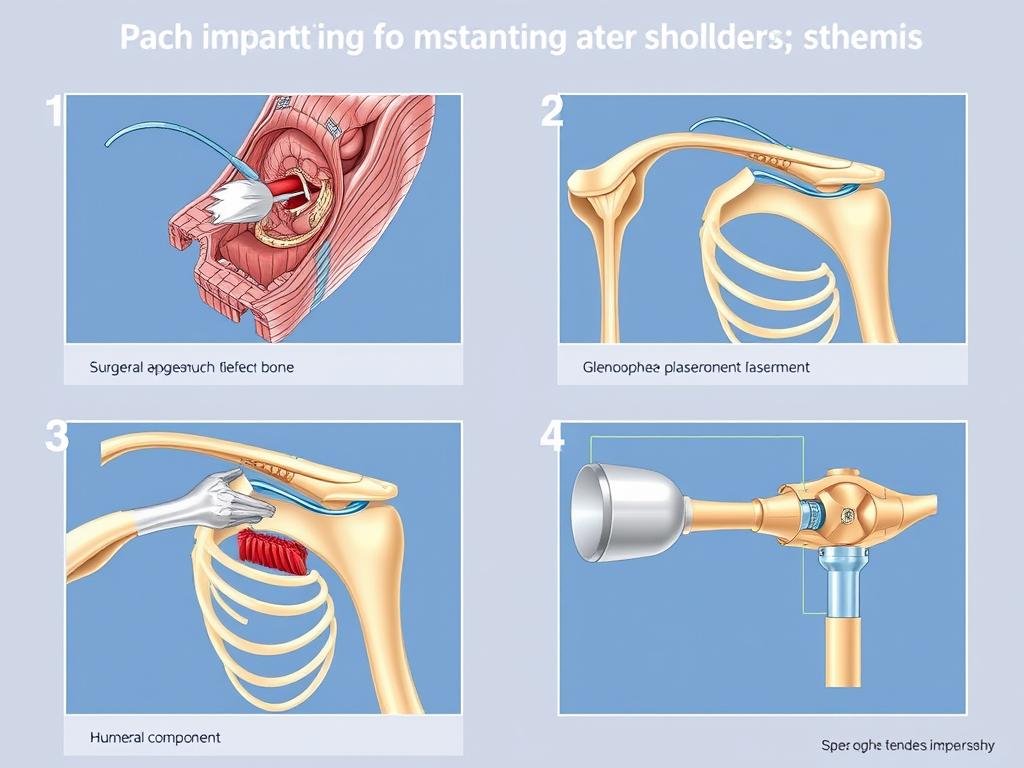

Ablauf der Operation einer inversen Schulterprothese

Die Implantation einer inversen Schulterprothese ist ein etablierter chirurgischer Eingriff, der von erfahrenen Schulterchirurgen durchgeführt wird. Ein gründliches Verständnis des Verfahrens kann Ihnen helfen, sich besser auf die Operation vorzubereiten.

Die Operation wird von spezialisierten Schulterchirurgen durchgeführt und dauert etwa 1-2 Stunden.

Operationsschritte

- Die Operation erfolgt in der Regel unter Vollnarkose, in Ausnahmefällen ist auch eine regionale Betäubung möglich.

- Der Chirurg macht einen etwa 7-8 cm langen Schnitt an der Vorderseite der Schulter.

- Der Deltamuskel wird beiseite geschoben oder entlang seines Faserverlaufs geteilt.

- Die Sehne des Musculus subscapularis wird abgelöst, um das Schultergelenk freizulegen.

- Der geschädigte Oberarmkopf wird entfernt und der Knochen für die Aufnahme der Pfannenkomponente vorbereitet.

- Die Gelenkpfanne am Schulterblatt wird präpariert und die kugelförmige Komponente befestigt.

- Die Pfannenkomponente wird am Oberarm befestigt, meist zementfrei.

- Die Komponenten werden zusammengefügt und auf korrekte Funktion geprüft.

- Die Weichteile werden wieder befestigt und die Wunde verschlossen.

Die einzelnen Schritte bei der Implantation einer inversen Schulterprothese.